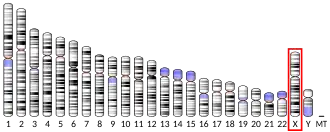

MECP2 (methyl CpG binding protein 2) is a gene[5] that encodes the protein MECP2.[6] MECP2 appears to be essential for the normal function of nerve cells. The protein seems to be particularly important for mature nerve cells, where it is present in high levels. The MECP2 protein is likely to be involved in turning off ("repressing" or "silencing") several other genes. This prevents the genes from making proteins when they are not needed. Recent work has shown that MECP2 can also activate other genes.[7] The MECP2 gene is located on the long (q) arm of the X chromosome in band 28 ("Xq28"), from base pair 152,808,110 to base pair 152,878,611.

MECP2 is an important reader of DNA methylation. Its methyl-CpG-binding (MBD) domain recognizes and binds 5-mC regions. MECP2 is X-linked and subject to X inactivation. MECP2 gene mutations are the cause of most cases of Rett syndrome, a progressive neurologic developmental disorder and one of the most common causes of cognitive disability in females.[8] At least 53 disease-causing mutations in this gene have been discovered.[9]